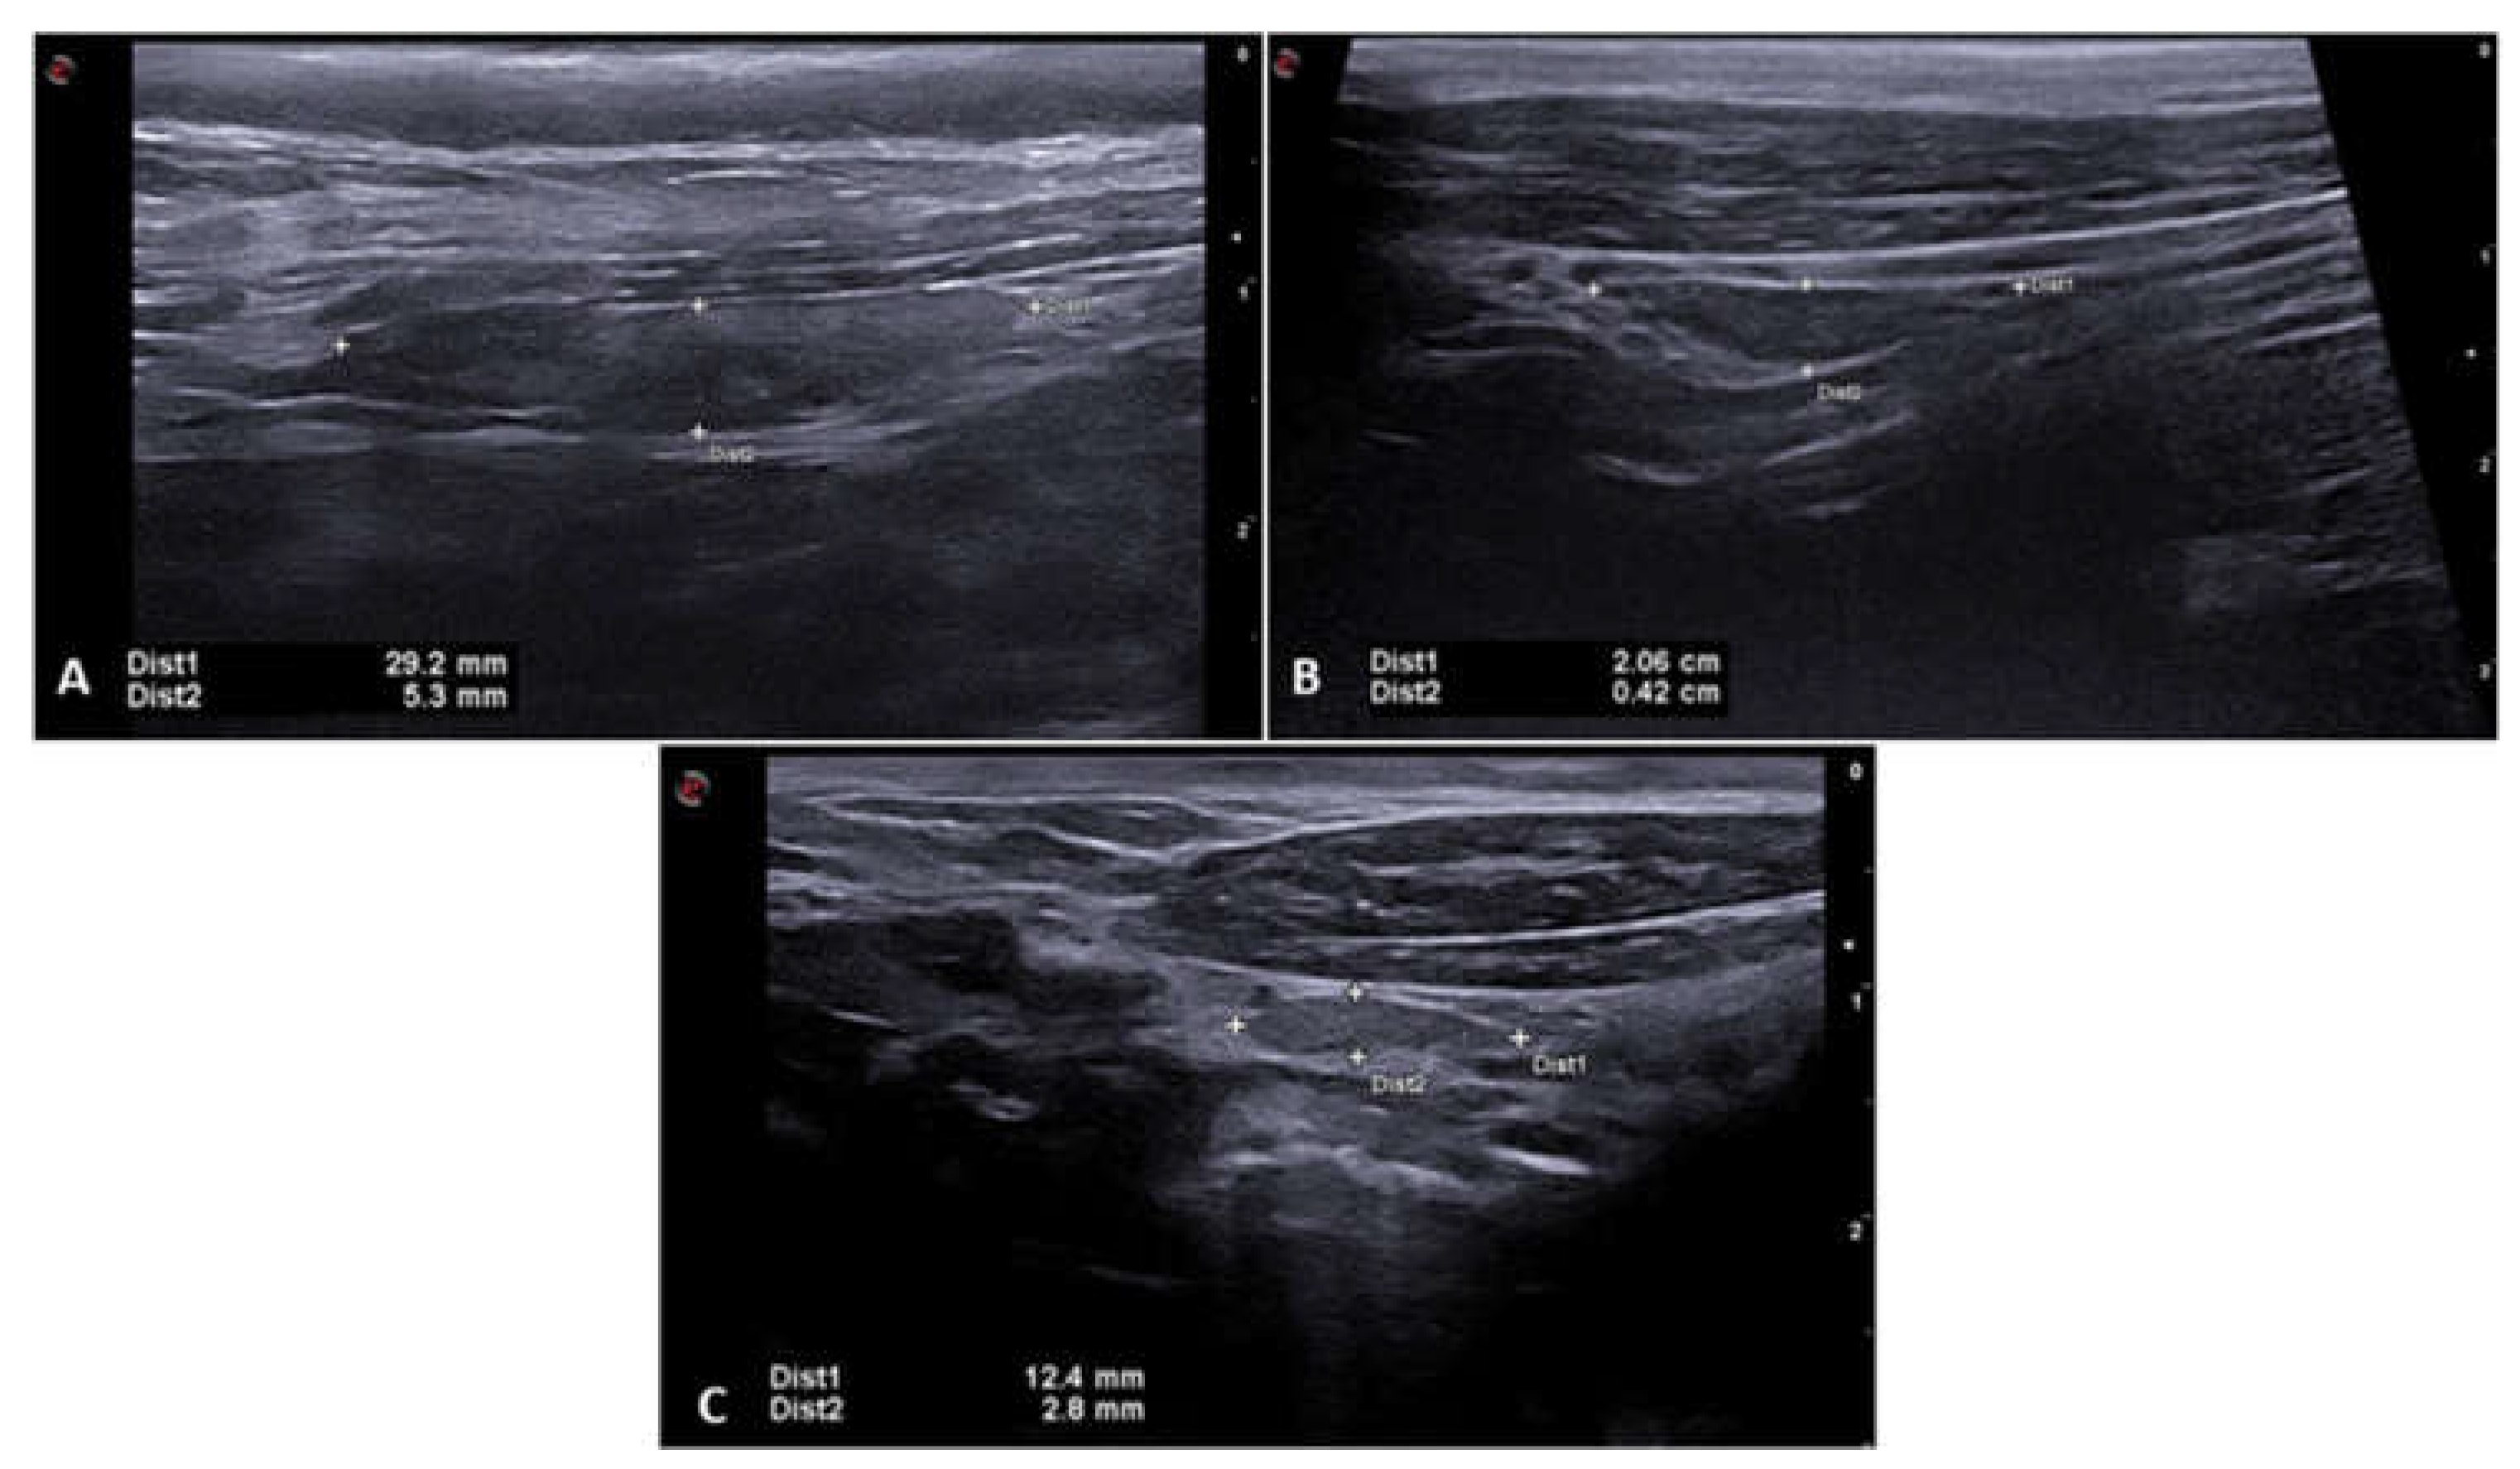

3.3. Small, Medium and Large Sized Dogs

To assess whether the size of the dogs influenced the quantitative B-mode ultrasound and elastographic characteristics, the animals were separated into groups according to their size: large (G), medium (M) and small (P). The large size group was made up of dogs weighing 25 to 30 kg, medium size from 15 to 24 kg dogs and the small size from 3 to 14 kg dogs. According to this parameter, a significant difference and positive correlation was found between size and width (p=0.0031), length (p=0.004) and depth (p=0.0007) between the large size group and the medium and small size groups. Figure 6 shows B-mode ultrasound images of the thyroid lobes of dogs from different sizes with the respective width and length dimensions in a longitudinal section. Figure 6A, 6B and 6C show one of the thyroid lobes of large, medium and small size dogs. The difference between the shear wave velocities of the thyroid between the sizes of dogs was not significant between the different groups that took part in this study. Table 3 shows B-mode values for each size and elastographic ultrasound characteristics.

Figure 6. - B-mode ultrasound image of the thyroid lobe with the calipers positioned over the lobe to measure length (Dist1) and width (Dist2) in different size dogs. (A) Left thyroid lobe of a large dog. (B) Left thyroid lobe of a medium-sized dog. (C) Right thyroid lobe of a small dog.